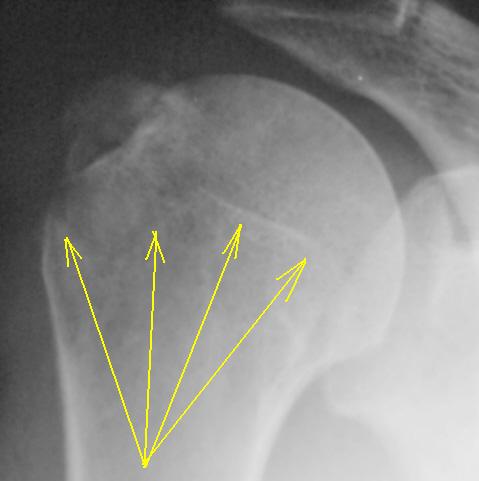

Вот то, что отмечено желтыми стрелочками на последней серии снимков - и есть отрыв большого бугорка. Такой большооооой отрыв большоооооооого бугорка.

Согласен с Вами Анна. "Ну очень большой".

С большим бугорком более-менее понятно. Вопрос: где малый?